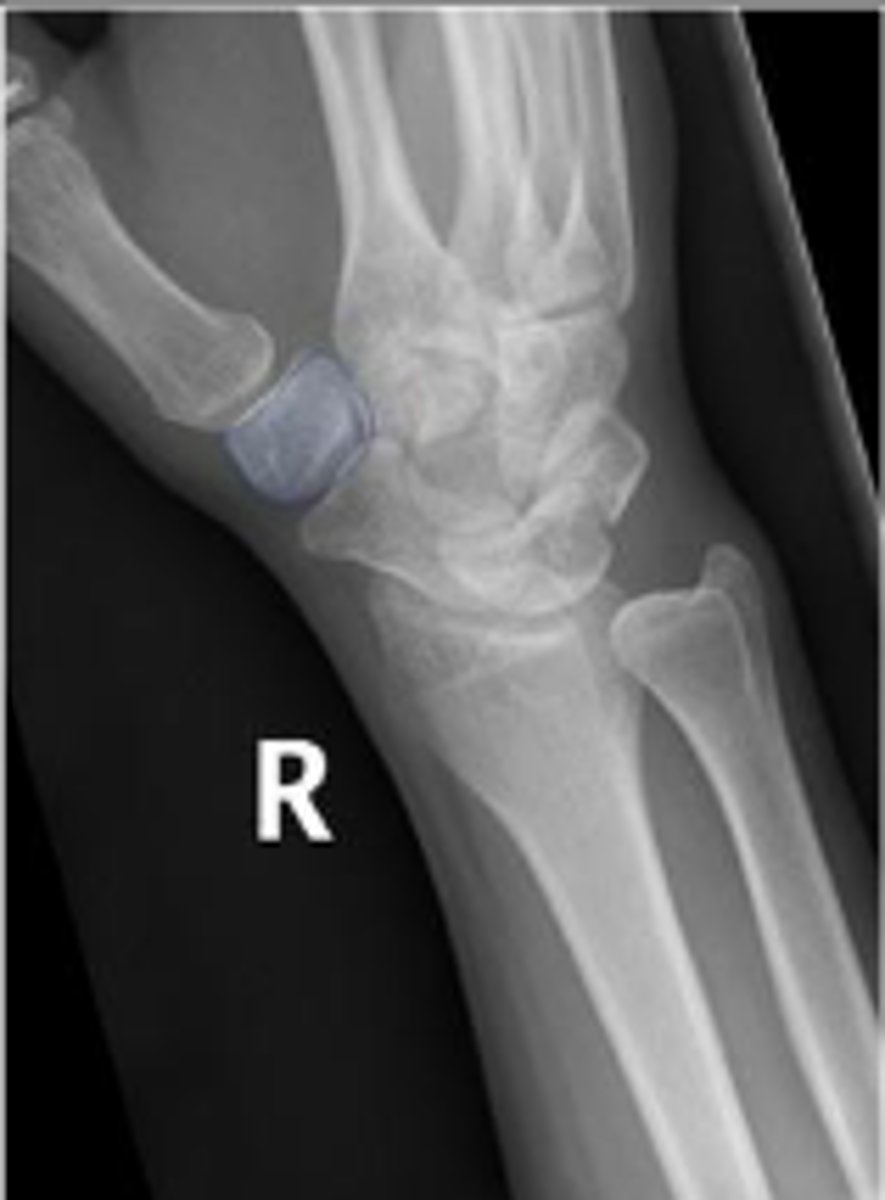

Medial oblique of the right wrist

What is the name of the radiographic view?

Right scaphoid

What is outlined?

Right trapezium

Right triquetrum

Right pisiform

What is the arow pointing to?